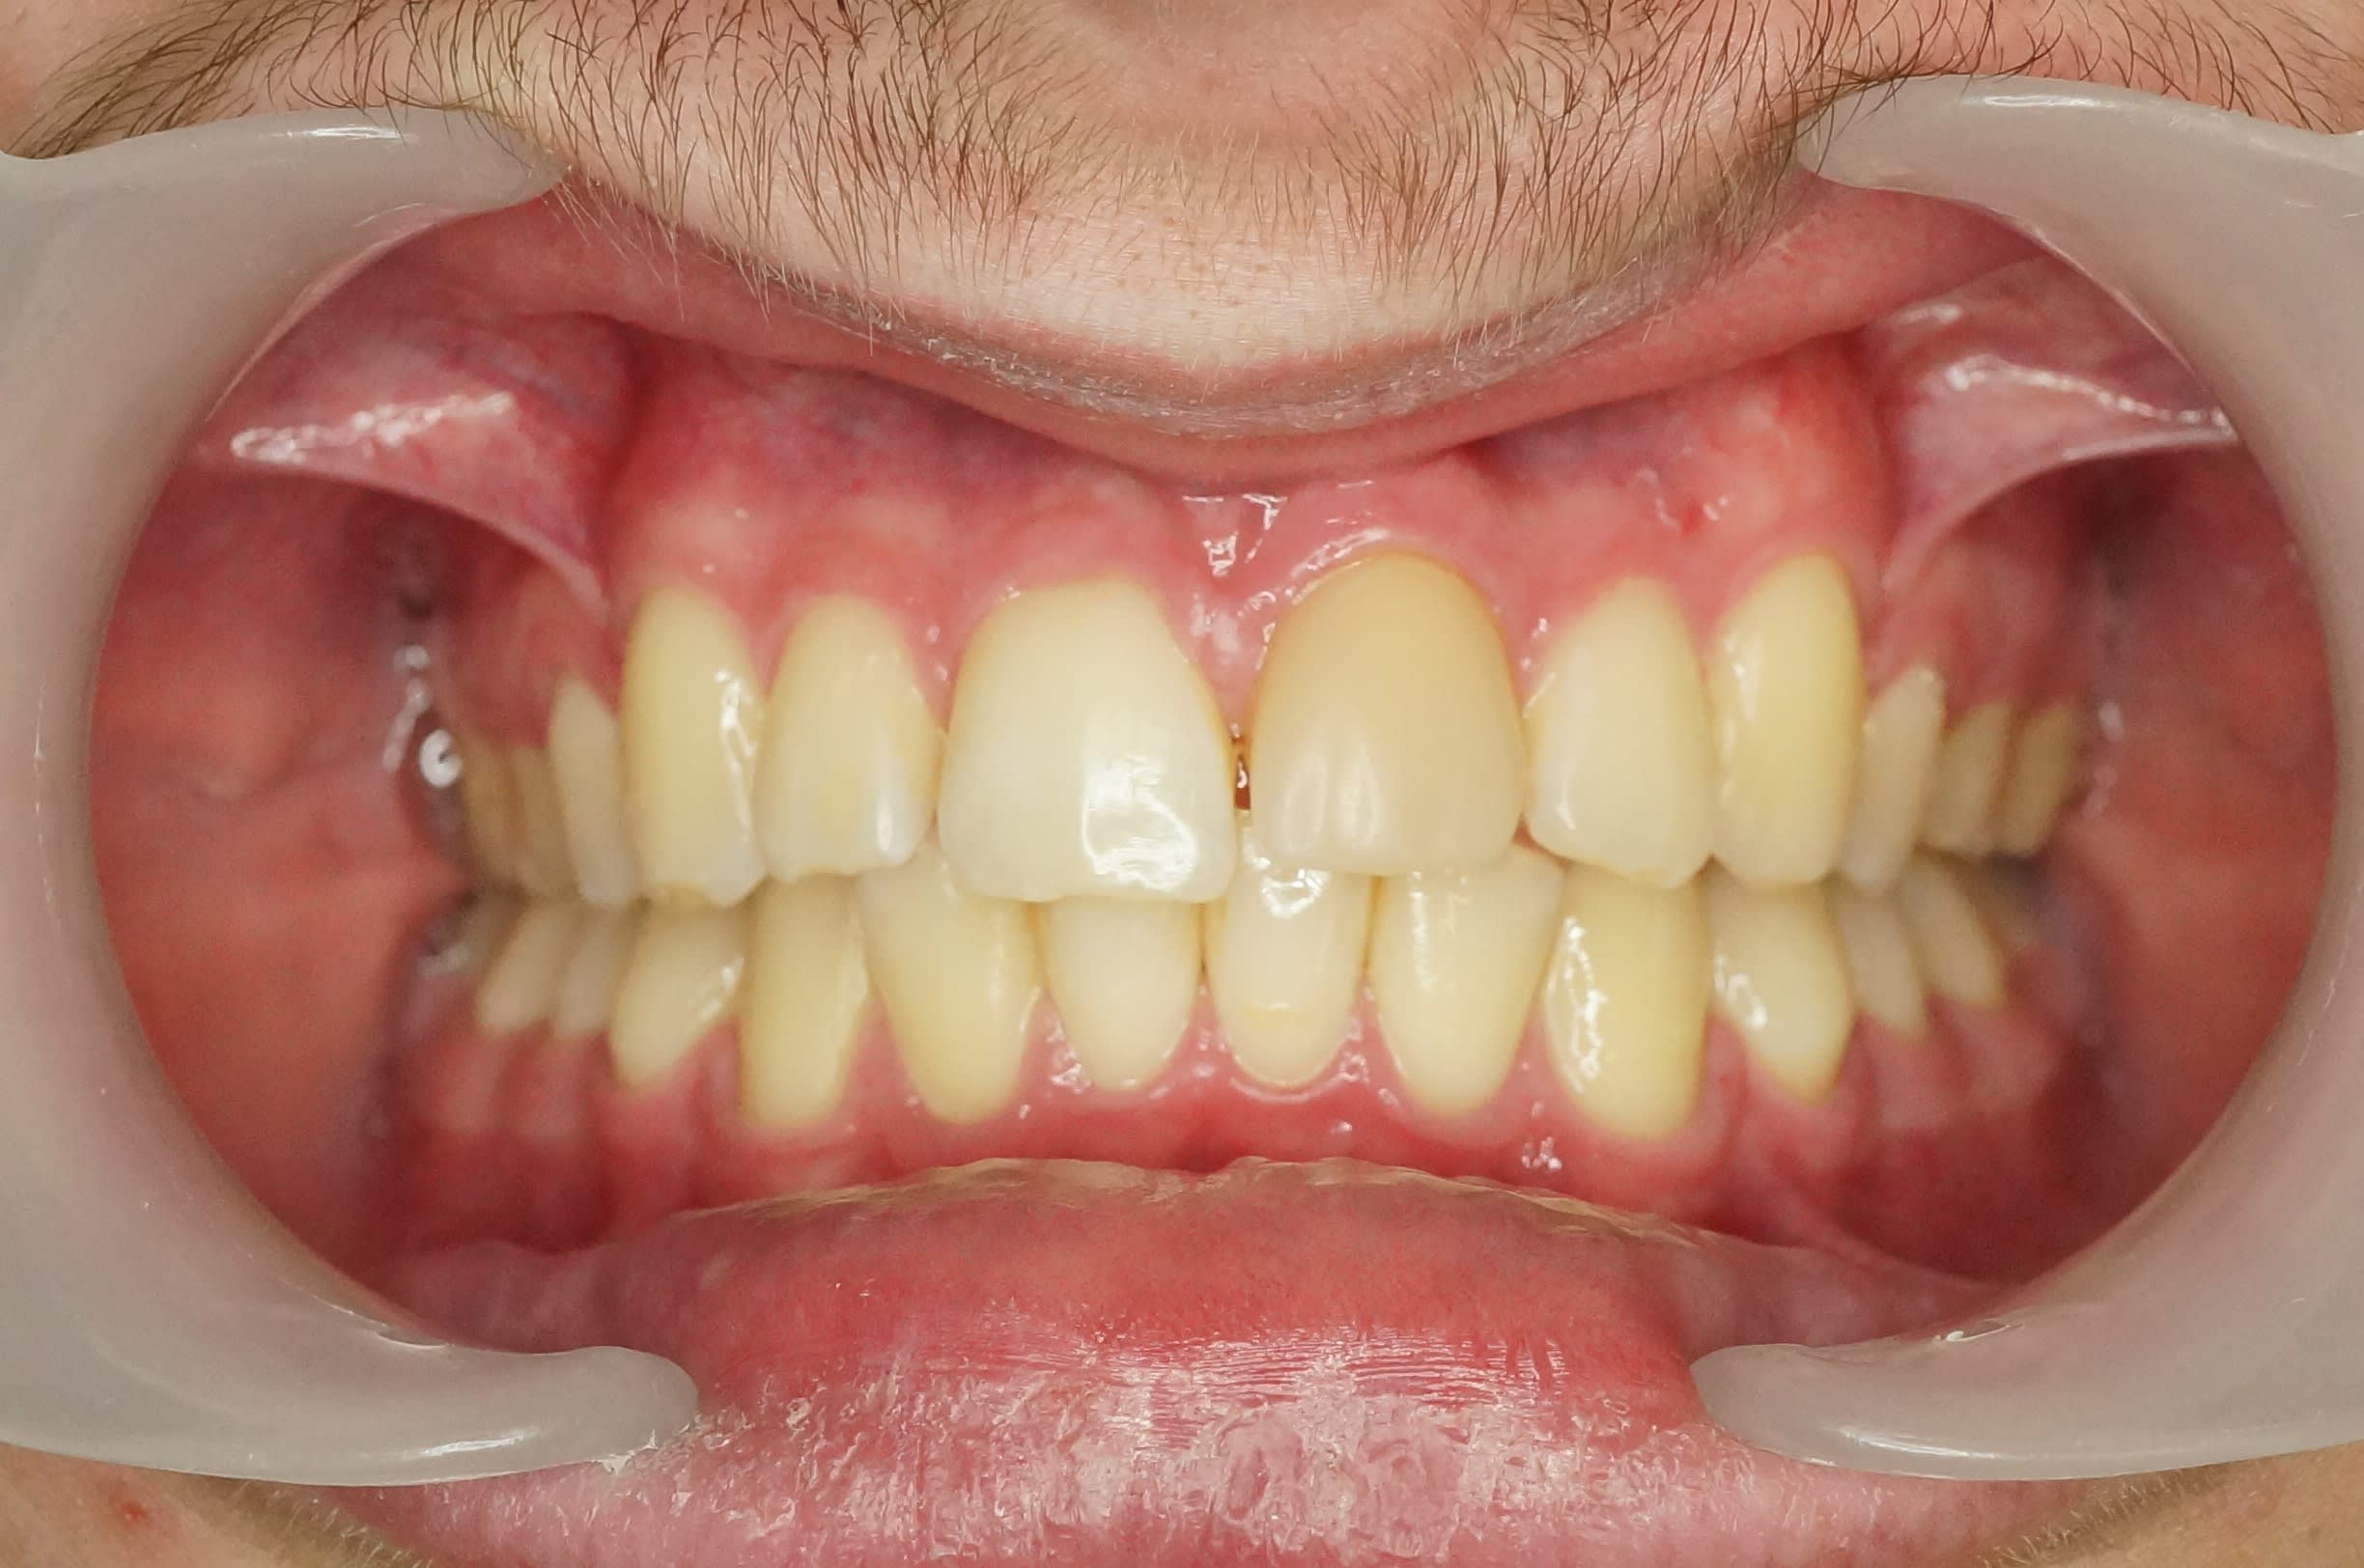

Dans ton cas de macrodontie, je trouve le résultat esthétique loin d’être désastreux. La ligne des collets est belle et la morphologie de la 21 de substitution pourrait être revue facilement avec une facette.

> Dans ton cas de macrodontie, je trouve le résultat esthétique loin d’être

> désastreux. La ligne des collets est belle et la morphologie de la 21 de

> substitution pourrait être revue facilement avec une facette.

Tu as raison, c'est esthétiquement améliorable de face, cependant son épaisseur la rend trop vestibulaire.

Cela se voit bien ça sur la vue occlusale.